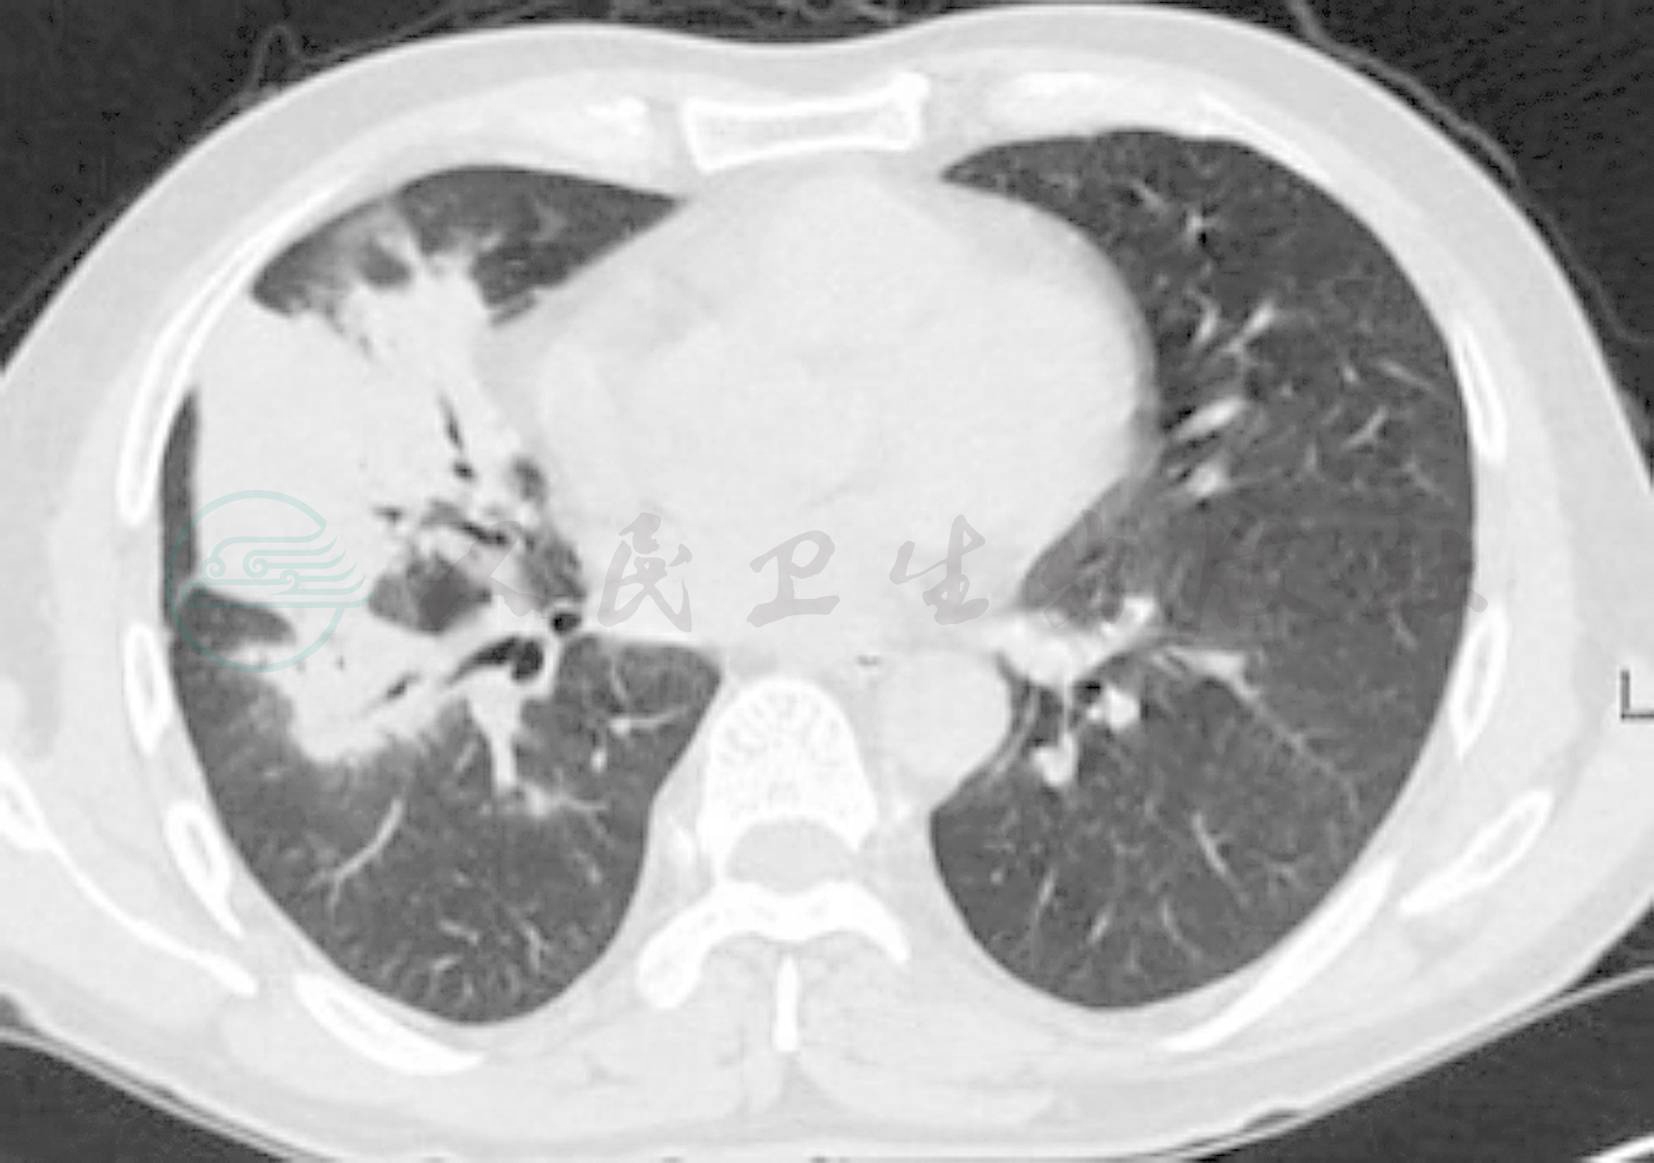

患者男性,65岁,因“咳嗽1周”于2011年6月2日入院。患者受凉后出现咳嗽,主要为干咳,无明显咳痰,无发热、盗汗、胸痛、咯血等不适。当地医院PPD皮试(-),肺部CT示:右上肺斑片状密度增高影,右中叶大片状密度增高影,其内可见充气支气管征(图1),未治疗。以“肺炎”收住院。

图1 入院前肺部CT